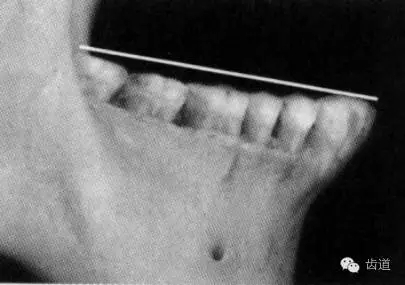

借助平面鏟,可以極為便利地形成光滑平整的HE平面。

常見(jiàn)的黃金鏟,后端有5毫米卷邊,按圖示的方法形成上頜平面非常容易。但是卷邊的反面端頭是圓角,所以用在下頜時(shí)就不太方便。

展示一下局長(zhǎng)改良的鏟子,方形,無(wú)論上頜還是下頜,一把鏟子都能應(yīng)付自如。